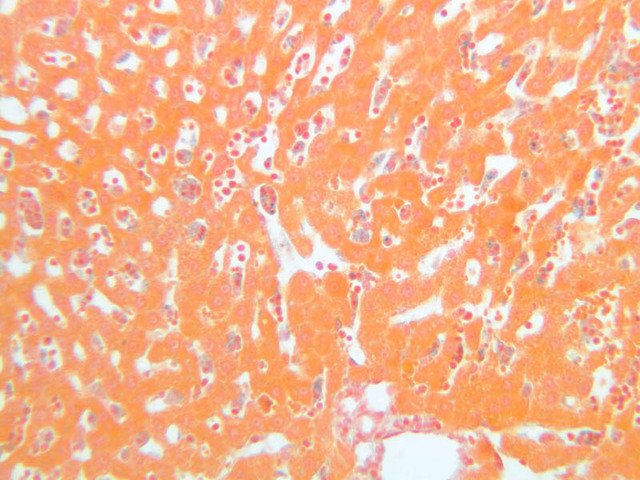

A section of liver from an animal injected with trypan blue appears on slide B-28 ([10x, 20x, 40x-labeled] [40x] [20x, 40x] [40x]). Even though the staining of this section has a very washed out appearance, it is still possible to identify a number of Kupffer cells that have ingested particles of the trypan blue dye.

13 Kupffer Cell KC TB b28 kupffer cells liver 40x orange blue labeled.jpgB28, Liver, 40x

14 Red Blood Cell RBC TB b28 kupffer cells liver 40x orange blue labeled.jpgB28, Liver, 40x